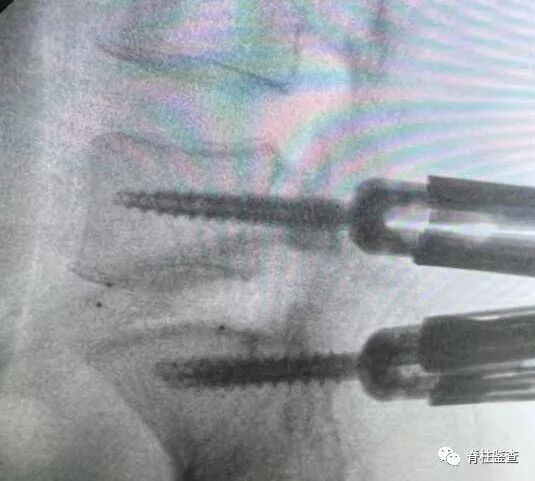

• 置入椎弓钉螺钉

• 置入长度及弯度适中的钉棒